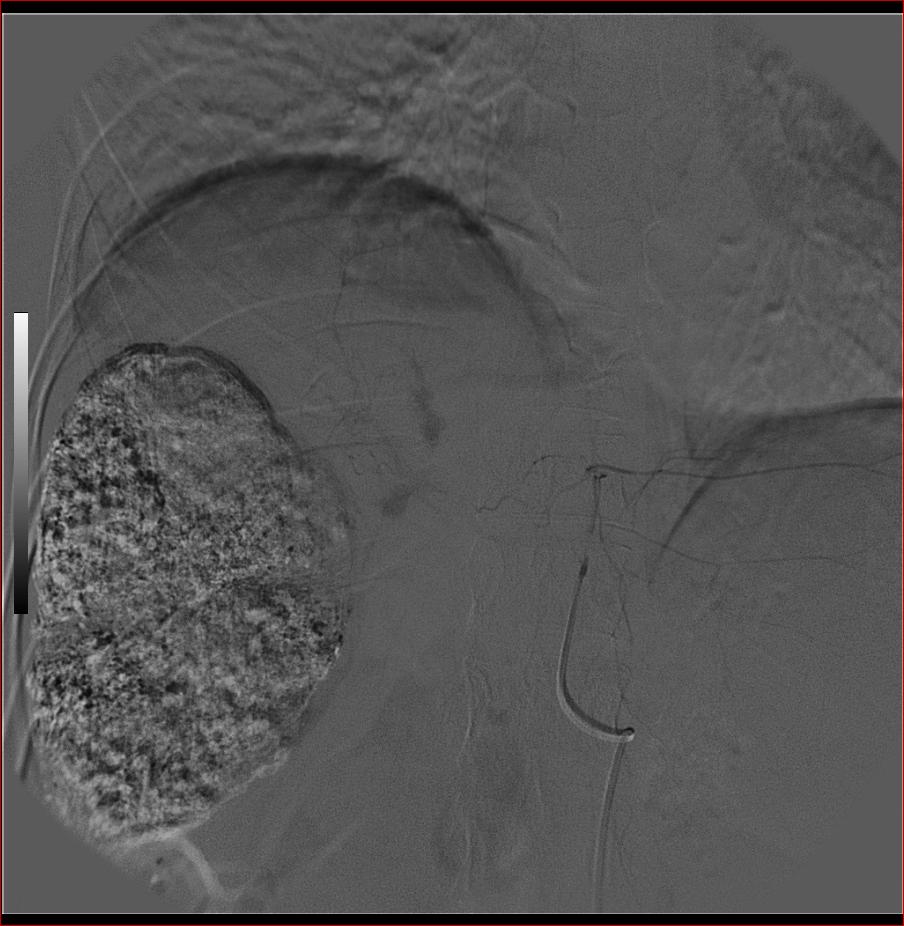

第二次(50天后)

栓塞的非常理想。

巨块型肝癌介入术后,肝左叶有转移吗(第二次进行肝左动脉栓塞了吗?)